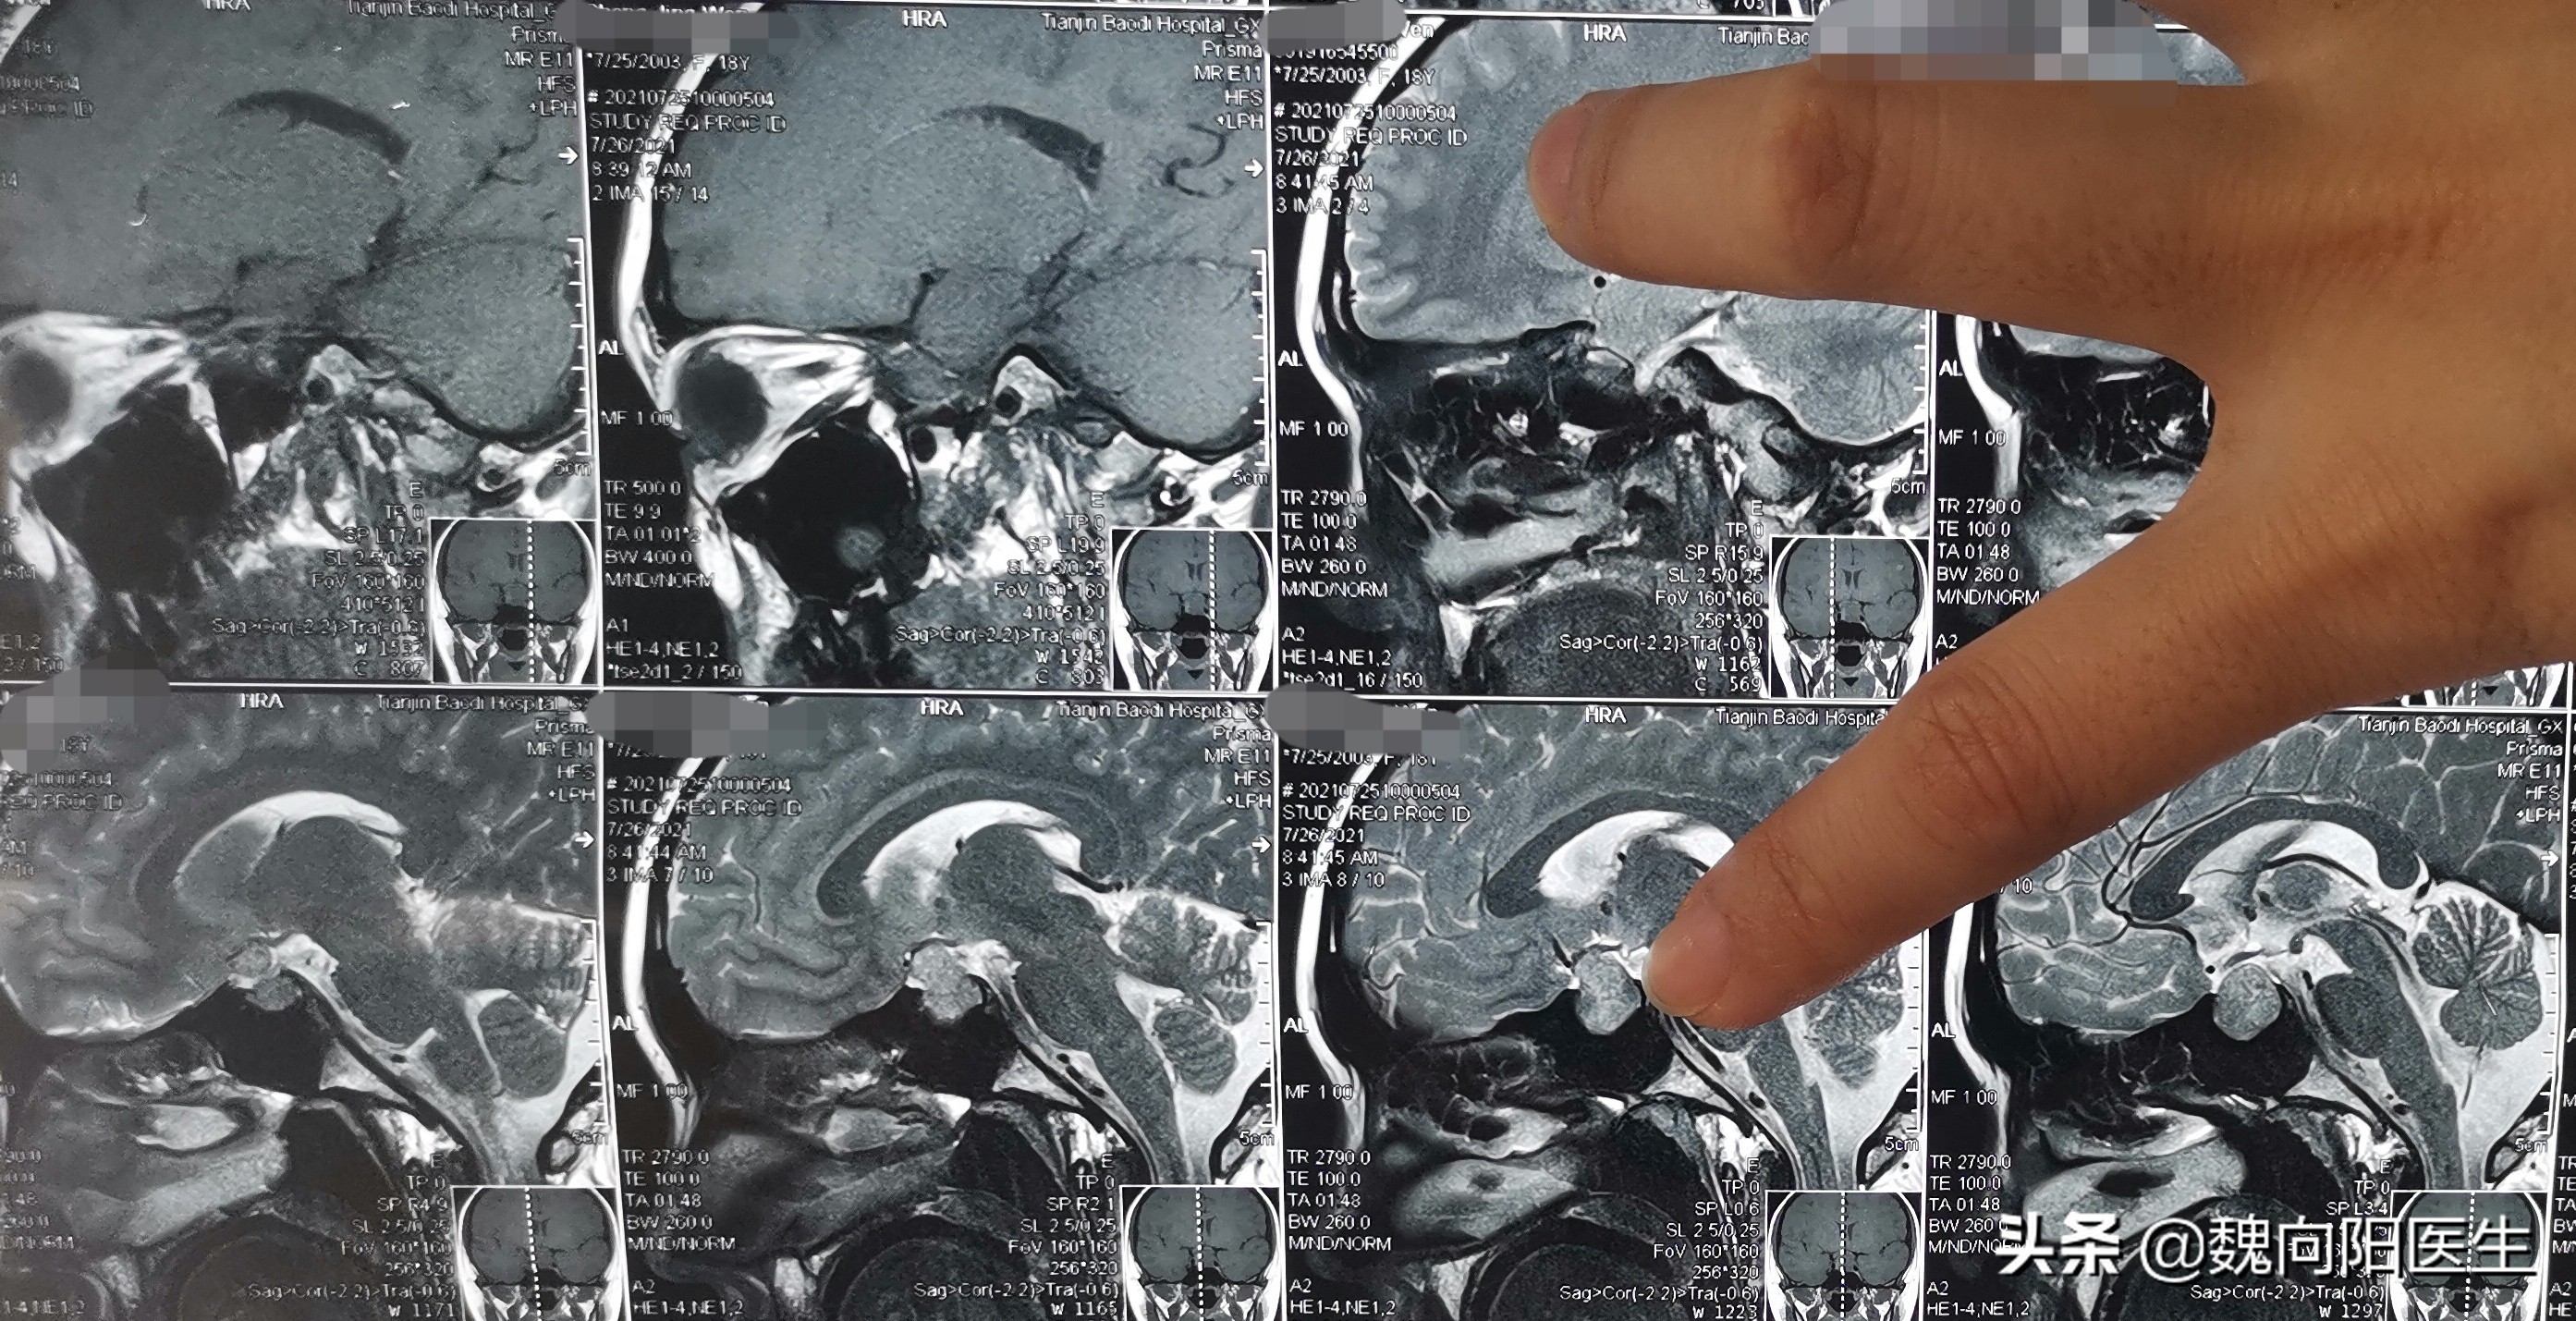

高考终于考完了,父母才领着小女孩来医院检查,头MRI发现是:“垂体瘤”。

垂体瘤